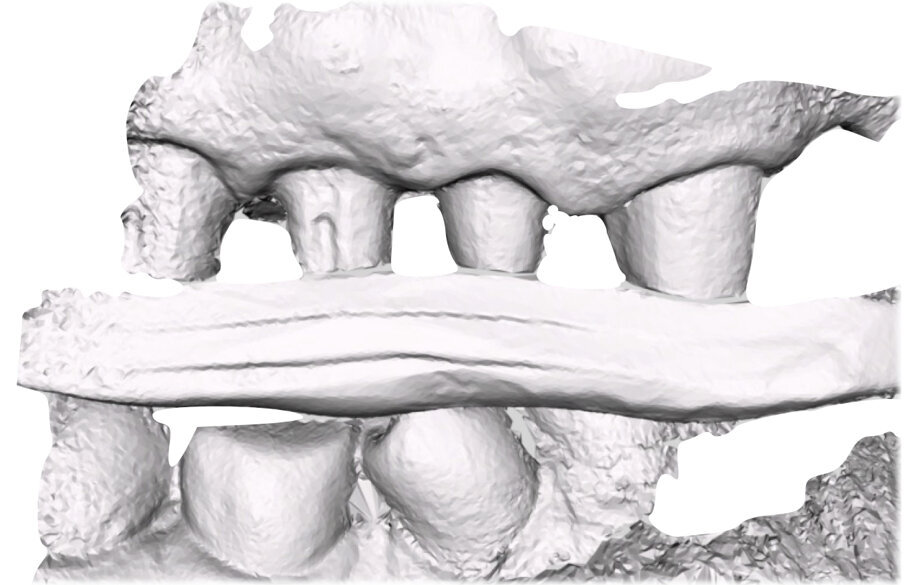

Si esegue perciò cefalometria (Fig. 8) su radiografia latero-laterale (Fig. 9) e axiografia dei movimenti limite (Cadiax Compact, Gamma Dental) (Fig. 10) per la programmazione di un articolatore a valori medi (Artex TR, AmmanGirrbach) e montaggio dei modelli con arco faciale, che confortano nella produzione di un primo provvisorio prelimatura con rialzo arbitrario della VDO di 5 mm sull’asta incisale e miglioramento di OB e OJ, a scopo pre-terapeutico interlocutorio e di immediata risoluzione estetica. Conclusa la necessaria terapia causale e restaurativa viene eseguita la scansione intraorale delle arcate (TRIOS 3 Pod, 3Shape) (Figg. 11-14) e del rapporto articolare con cera di RP (Fig. 15). La scansione è stampata (VisiJet RWT, 3D Systems) con monconi sfilabili tramite stampante 3D (ProJet MJP 2500 Plus, Selltek) (Figg. 16-20), i modelli derivanti sono zoccolati e montati con cere di RP e arco faciale su articolatore a valori individuali (Reference SL, Gamma Dental). La programmazione dell’articolatore derivante dalla registrazione axiografica è ora eseguita come da indicazioni del software (Gamma Dental software, sia per l’uso degli inserti condilari ed incisali, sia per la definizione degli angoli di SCI e di Bennet (Fig. 21). Lo spazio protesico risultante a una VDO adeguata alla riabilitazione dei denti anteriori vitali, con anatomia non ulteriormente modificabile, è insufficiente per uno stabile ripristino dei rapporti occlusali, specie nei tragitti funzionali. Si decide perciò di impiegare due inserti rossi di programmazione di protrusiva (+2 mm) per riposizionare la mandibola in TRP (Figg. 22, 23).

Ciò consente un miglioramento dei rapporti interarcata, un guadagno di spazio protesico in regioni premolari e molari, ed il mantenimento di uno spazio protesico conforme ad una corretta anatomia per i denti vitali da 1.3 a 2.3. Al paziente viene pertanto aggiornato il piano di trattamento e proposta la riabilitazione in TRP, con la previsione di overlays all’arcata inferiore per costruzione del nuovo piano occlusale. In posizione terapeutica sono modellati i coni delle centriche attive sui monconi sfilabili all’arcata inferiore, per la successiva individuazione al CAD con modulo articolatore del piano occlusale studiato. Questo rapporto articolare in TRP è ora scansito con scanner da laboratorio Xanos Evo Scan Compact (Fig. 24).

I modelli sono così importati in corretta posizione spaziale tramite il modulo exocad Virtual Articulator (Fig. 25). Non avendo a disposizione nel CAD l’analogo virtuale dell’articolatore Reference SL, viene impostato il sistema virtuale SAM, che usa lo stesso piano di riferimento axio-orbitale e geometria sovrapponibile al Reference SL. Per la programmazione virtuale dei parametri funzionali dell’articolatore si riesegue l’output dall’axiografia elettronica con Gamma Dental per SAM (Fig. 26). Si procede perciò ora con la modellazione CAD della ceratura mantenendo il riferimento dato dal piano occlusale individuato dai coni di centrica scansiti con l’articolatore (Fig. 27). L’articolatore virtuale consente una prima verifica dei rapporti occlusali tra gli elementi e un abbozzo di funzionalizzazione delle cuspidi con strumenti virtuali dinamici, che permette di arrivare ad un CAD design vicino alla morfologia ricercata (Figg. 28-33). Il modellato è ora fresato in cera Yeti Dental al CAM con fresatore VHF Cam5-S1 ed i denti in cera, tutti singolarmente sfilabili, sono posizionati sui modelli eseguiti con stampa 3D.